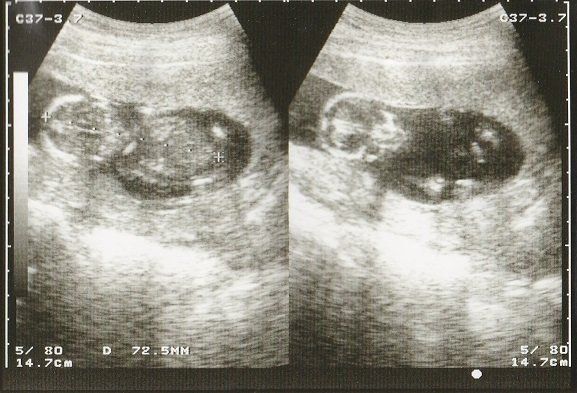

妊娠18週目のエコー写真 画像におさまらないほどに成長する

赤ちゃんがどんどん大きくなり、1枚の超音波画像ではおさまりきらなくなりました。画像を2枚くっつけて赤ちゃんの大きさを測っています。

BPD(児頭大横径=頭の直径)を測って、胎児の発育を調べるようです。ここまで、母子ともに特に異常も無く過ごせました。